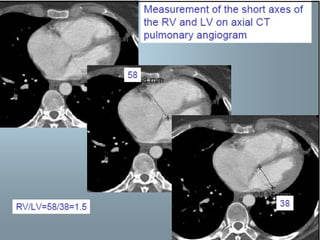

CT evidence of RV dysfunction

 RV/LV short axis >1= pulmonary

hypertension

 RV/LV short axis >1.5= severe PE

 Leftward septal bowing